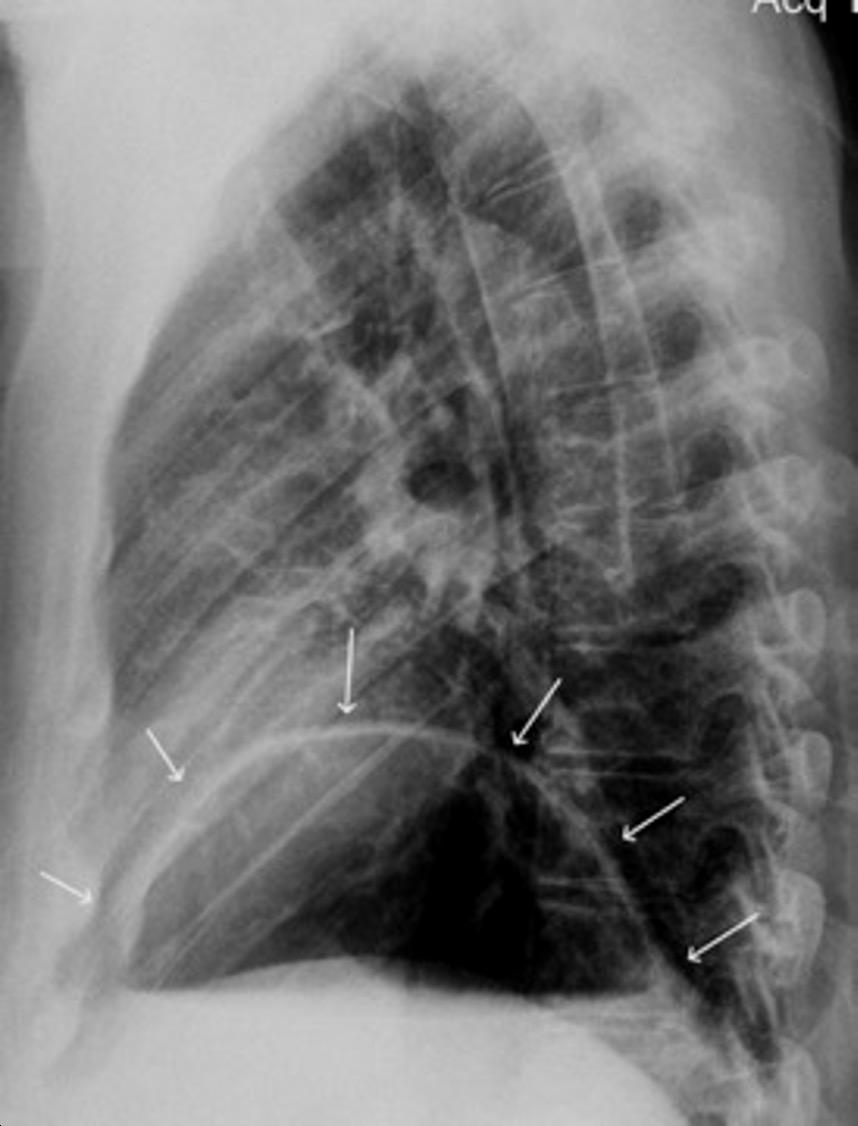

T. mixto de células germinales del testículo izquierdo

Nódulos pulmonares múltiples. (flechas verdes). Masas paratraqueales. (flechas amarillas). Dudoso ensanchamiento retrocrural (flechas negras). sigue….

Ttawfik A et al. Trans-diaphragmatic Pathologies: Anatomical Background and Spread of Disease on cross-sectional Imaging. Current Problems in Diagnostic Radiology. 2021.

T. mixto de células germinales del testículo

izquierdo Metástasis pulmonares. (flechas verdes). Ganglios paratraqueales. (flechas amarillas). Ganglios retroperitoneales (flechas negras)

Tawfik A et al. Trans-diaphragmatic Pathologies: Anatomical Background and Spread of Disease on cross-sectional Imaging. Current Problems in Diagnostic Radiology. 2021.